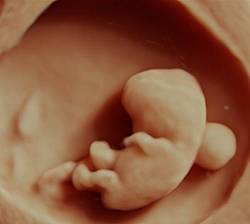

6. bis 16. SSW